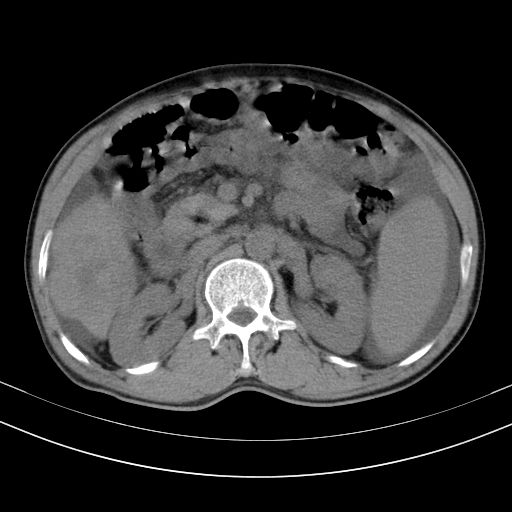

以下是引用随光逐影在2010-2-28 10:23:00的发言:[br]1)考虑肝癌;建议行ct增强扫描检查。2)肝硬化,脾大,腹水。3)慢性胆囊炎。

以下是引用dyqct在2010-2-28 16:44:00的发言:[br][quote]以下是引用随光逐影在2010-2-28 10:23:00的发言:[br]1)考虑肝癌;建议行ct增强扫描检查。2)肝硬化,脾大,腹水。3)慢性胆囊炎。